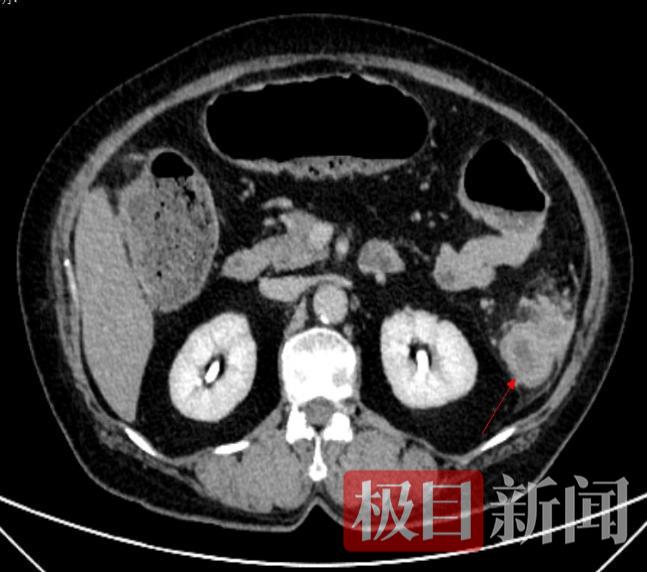

60岁的王女士5天没有排气排便,腹痛腹胀得痛苦不堪,被家属紧急送至家附近的湖北省中医院就诊。胃肠外科曹钧副主任医师、孙相钧主治医师会诊后,通过询问患者病史和查体,初步判断王女士为急性肠梗阻,病情危急,需要紧急解除肠梗阻。在迅速完善相关检查后,腹部增强CT提示:降结肠肿瘤导致的肠梗阻,肿瘤考虑恶性可能,升结肠及横结肠积气积便严重。

红箭头处可见降结肠肿瘤